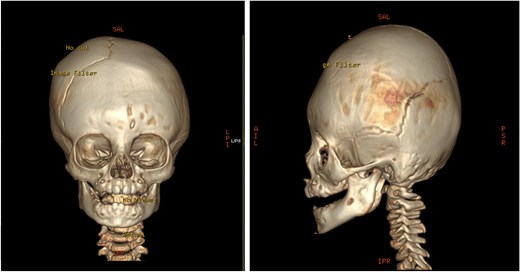

An 11-month-old female infant, born to unrelated Saudi parents, was referred to our facility with unilateral left coronal craniosynostosis, congenital microcephaly, global developmental delay, and a confirmed ZIC1 gene mutation. Comorbidities included a patent foramen ovale, aortopulmonary collateral vessel, G6PD deficiency, and gastroesophageal reflux disease (GERD). At birth head circumference was 29 cm (<first percentile), and progressive skull asymmetry and squinting were noted over time. Developmentally, she exhibited delayed gross and fine motor skills with limited object transfer. On examination, she was alert and visually tracking, with inward ocular deviation (esotropia). Head circumference was 37 cm (<first percentile) with anterior plagiocephaly and towering of the left frontal region (Fig. 1). Pupils were equal and reactive. Fundoscopy and cranial nerve examinations were unremarkable. Gross motor power was within normal limits, except for moderate lower limb spasticity. 3D reconstruction computed tomography (CT) confirmed premature fusion of the left coronal suture with subtle elevation of the superolateral orbital rim, indicating harlequin sign (Fig. 1). Brain CT showed corpus callosum agenesis, colpocephaly, mild ventriculomegaly, right cerebellar and pontine hypoplasia, and a large cisterna magna, consistent with the reported ZIC1-related malformation spectrum (Fig. 2). Given the progressive deformity and concerns of increased intracranial pressure that might be partially contributing to her neurodevelopmental delay, anterior cranial vault expansion with fronto-orbital advancement was performed jointly by the neurosurgery and plastic craniofacial teams (Fig. 3). Intraoperatively, left-sided dural tension was appreciated, indicating localized increased intracranial pressure. The orbital bandeau was reshaped and advanced, achieving immediate cosmetic improvement (Fig. 4). The patient tolerated the surgery well and recovered uneventfully. At her 4-month follow-up, she showed developmental progress including standing without support, purposeful hand use, and verbalization (“Baba”). At 6-month follow-up, brain CT revealed areas of bone resorption which led to the placement of a ventriculo-peritoneal shunt (Fig. 5). The known association of ZIC1 mutation with tethering of the cord prompted spinal magnetic resonance imaging (MRI) screening. Positive findings indicated an untethering procedure, which was successfully done (Fig. 6).

Pre-operative 3D reconstruction CT showing left plagiocephaly with towering, and a subtle harlequin sign.